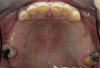

Initial examination revealed a partial edentulous patient with extensive wear of the maxillary anterior teeth and moderate wear in the mandibular teeth (Figure 1, Figure 2, Figure 3 , Figure 4, Figure 5, Figure 6 and Figure 7). The patient's maxillary and mandibular RPDs also showed excessive wear and multiple signs of fractures (Figure 2 and Figure 3). The patient had been wearing a mandibular nightguard for 8 years.

Figure 3  Intraoral occlusal view of mandibular dentition with the existing removable prosthesis presenting excessive signs of wear.

Figure 3